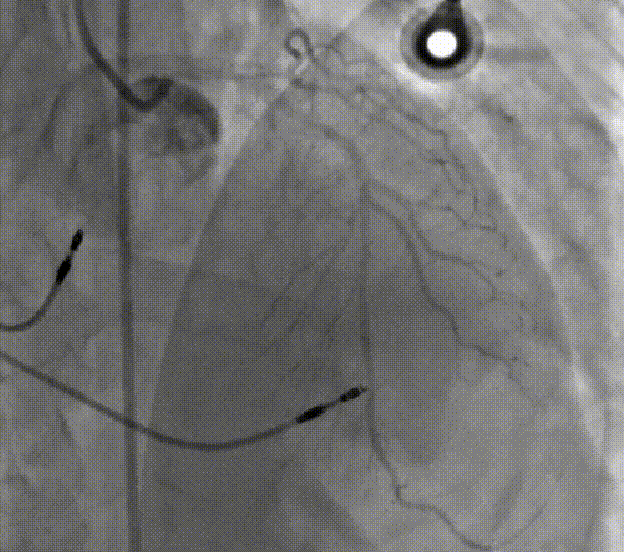

TAVR手术